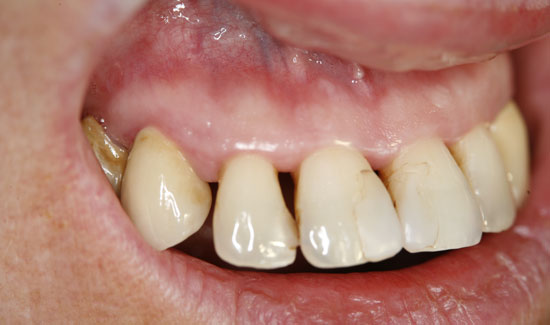

The patient introduced herself at our practice, inquiring about preserving the front teeth of her upper jaw, which were suffering from chronic periodontitis. We discovered general formation of pockets

(> 10 mm), spontaneous bleeding and a degree of tooth mobility of 2/3, i.e. the teeth were candidates to be extracted. As an interim solution (it was a public holiday) until restoration could take place, we offered local ozone gas treatment.

Fig. 2: Clinical aspect of region 12, formation of gas bubbles on the inflamed tissue. Continuous suction in the vicinity of the area of use